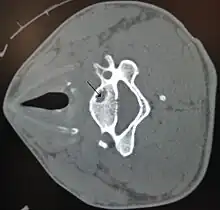

| A bone cyst in the vertebra of the neck as seen on CT | |

On CT scans, bone cysts that have a radiodensity of 20 Hounsfield units (HU) or less, and are osteolytic, tend to be aneurysmal bone cysts.[1]